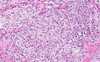

granulomatous inflammation

- classically seen in TB

- giant multi-nucleated Langerhan's cells may be seen